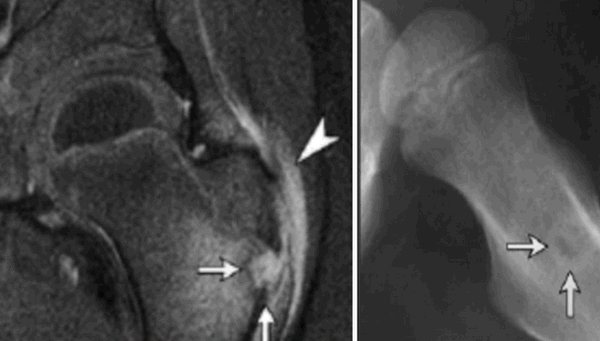

Диагностика

Ключевым методом в обследовании пациентов с МФКД является рентген, КТ и МРТ. При этом данные КТ позволяют более точно определить объём патологического очага и определить риск патологического перелома. МРТ выполняется чаще с целью дифференциальной диагностики.

Подострый остеомиелит на МР-скане и обычной рентгенограмме: отслойка надкостницы (наконечник), гнойный очаг (стрелки)